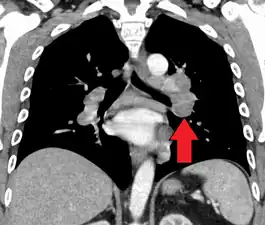

Hilar adenopathy especially on the person's left (coronal CT)

Chest radiograph changes are divided into four stages:[105]

- bihilar lymphadenopathy

- bihilar lymphadenopathy and reticulonodular infiltrates

- bilateral pulmonary infiltrates

- fibrocystic sarcoidosis typically with upward hilar retraction, cystic and bullous changes

Although people with stage 1 radiographs tend to have the acute or subacute, reversible form of the disease, those with stages 2 and 3 often have the chronic, progressive disease; these patterns do not represent consecutive "stages" of sarcoidosis. Thus, except for epidemiologic purposes, this categorization is mostly of historic interest.[28]